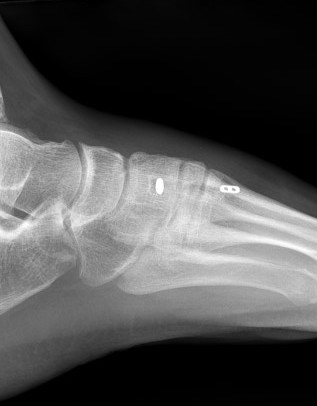

X-ray

Subtle widening of the medial cuneiform - 2nd metarsal distance, and the inter-metatarsal distance

Widening of the medial cuneiform - 2nd metatarsal distance, inter-metatarsal diastasis, fleck sign, possibly increased inter-cuneiform distance

Widening of the medial cuneiform - 2nd metatarsal distance, inter-metatarsal diastasis, fleck sign, increased inter-cuneiform distance